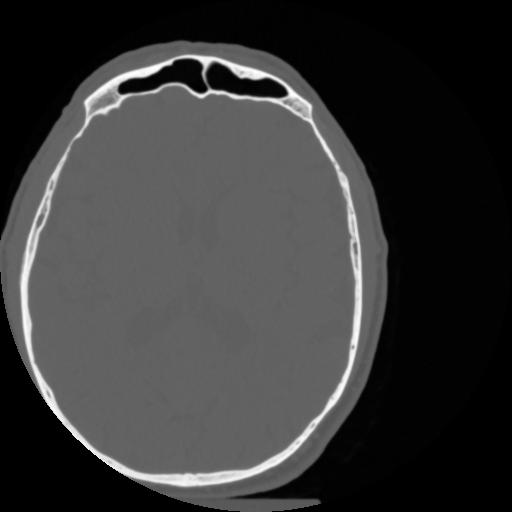

4 CEREBRO,,Vol,0.5,CEREBRO,,